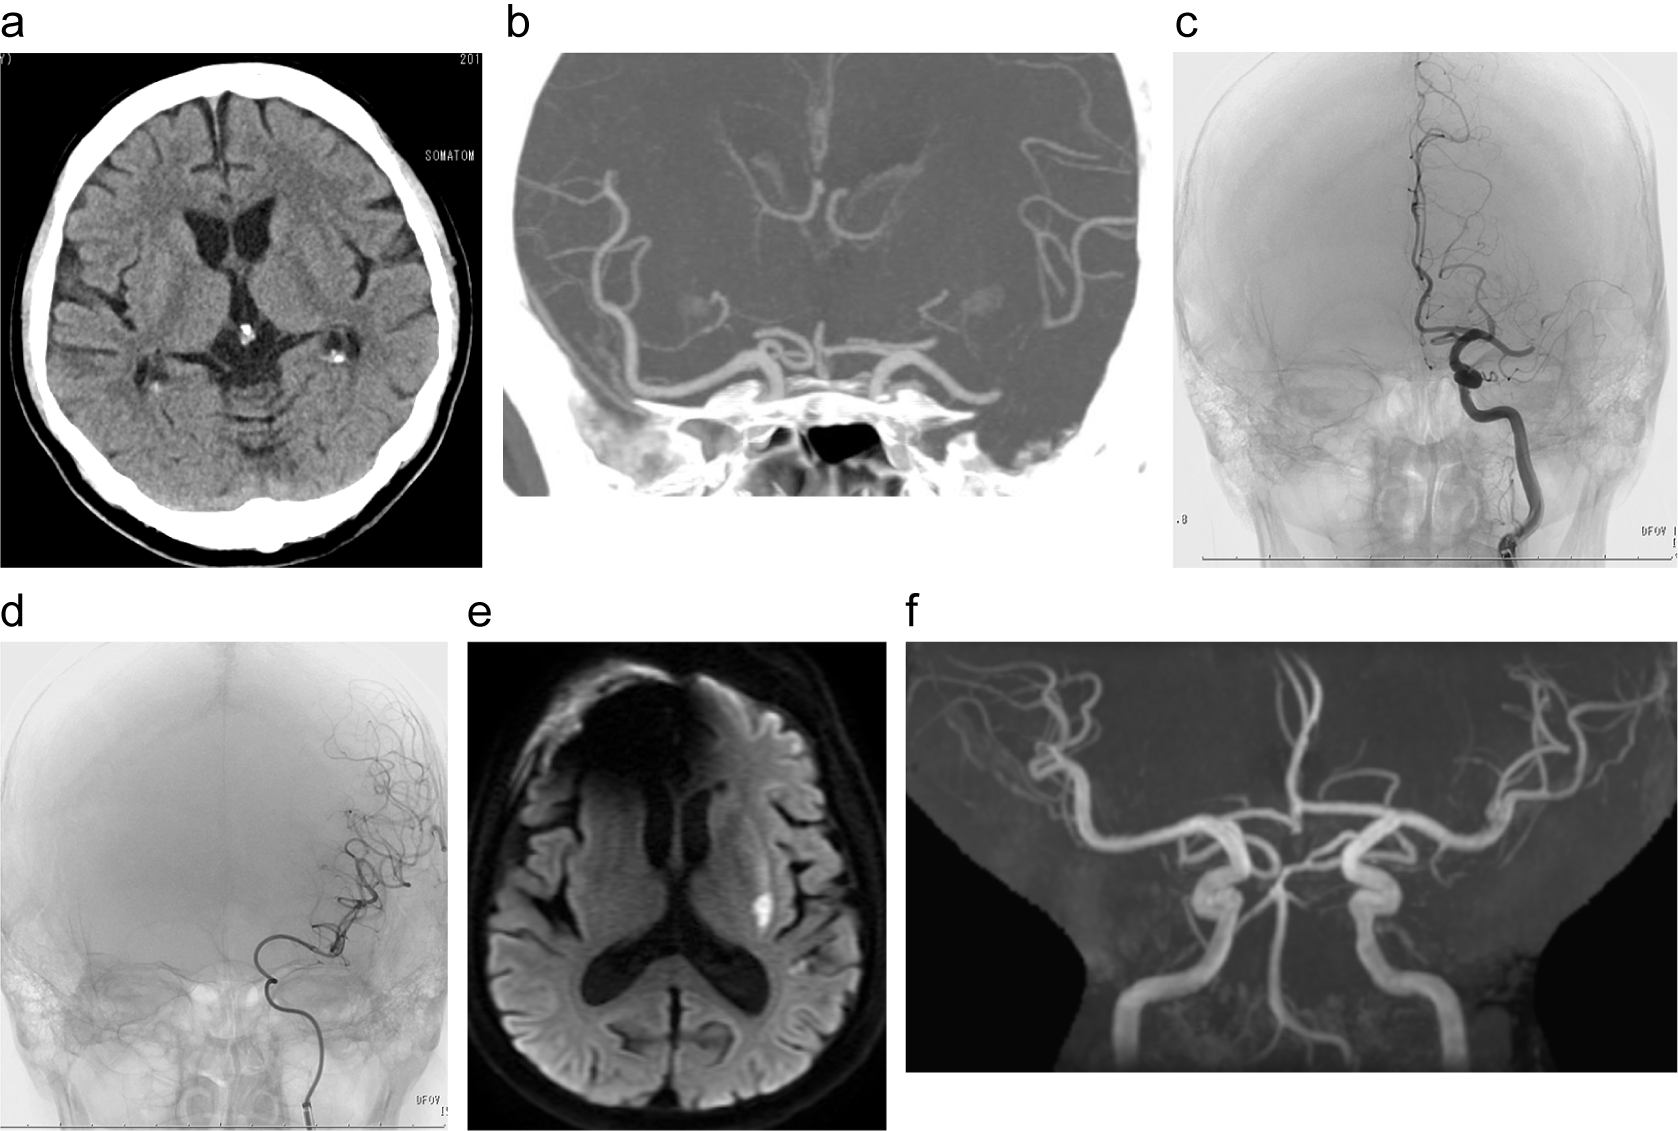

脳梗塞急性期の頭部CT、脳血管造影(機械的血栓回収療法前後)と翌日のMRI DWI画像

a:脳梗塞急性期の頭部CT

b:脳梗塞急性期のCTA

c:血管造影(機械的血栓療法前)

d:血管造影(機械的血栓療法後)

e:翌日のMRI DWI

f:翌日のMRA